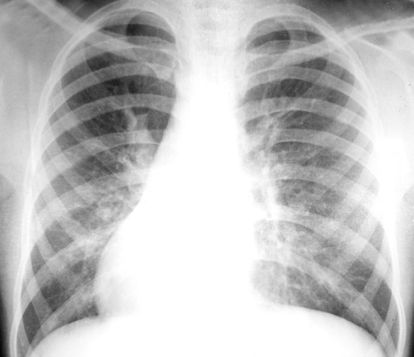

Lung of a child in respiratory failure and needs respirator for assist ventilation |